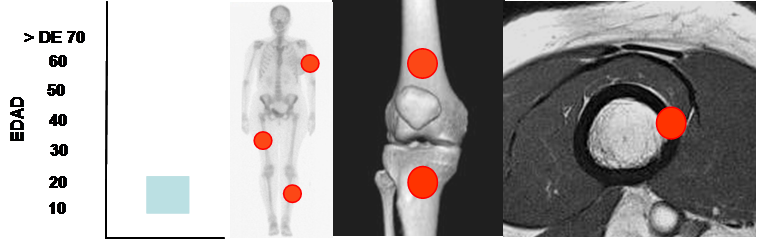

OSTEOMA OSTEOIDE.

Lesión benigna osteoblástica, caracterizada por un nido de tejido osteoide rodeado por esclerosis reactiva. (13).

La mayoría aparecen entre la 2º y 3º décadas y con el clásico de dolor nocturno, que cede con ASA. (13, 16, 17, 18).

Por definición son lesiones menores de 1.5 cm. Tumores mas grandes, corresponden a osteoblastomas. (13,17).

Es una lesión cortical, de la región metafisodiafisiaria de los huesos largos, con predominio en el fémur y la tibia. (16, 17). (Fig 58).

Fig 58. Osteoma osteoide.

Mayor frecuencia entre la 2º y 3º décadas. Predominio en los huesos largos.

Lesión metafisodiafisiaria, de ubicación cortical.